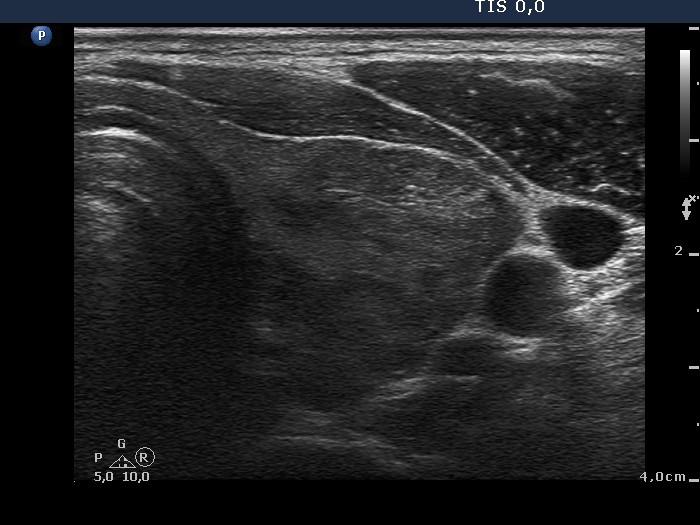

Ultrasonography: the thyroid was composed of minimally and moderately hypoechogenic and echonormal areas. None of the lesions fit to a nodule. The vascularization was moderately increased.